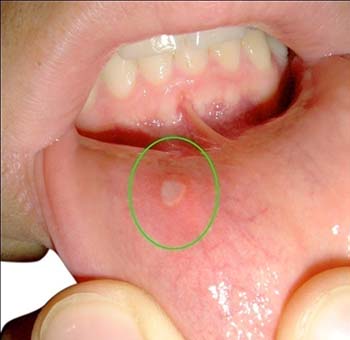

Aphthous Ulcers or Canker Sores

These are small, painful ulcers on the inside of the mouth, lips or throat that occur due to eating very spicy or hot food, vitamin deficiencies, hormones, stress, etc.